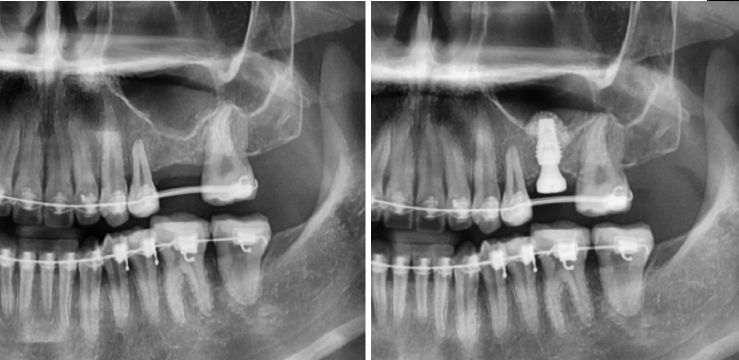

"윗 잇몸뼈가 부족해서 상악동 수술이 필요하다"는 이야기를 들어본 적 있으신가요? 임플란트 식립 시 윗니 어금니 부위의 잇몸뼈가 충분하지 않을 때 필요한 시술이 바로 상악동 수술(상악동 거상술, 상악동 뼈이식)입니다. 이백점치과는 고난이도 상악동 수술도 안전하고 성공적으로 진행하여 환자분들께 건강한 임플란트를 선사합니다. CASE. 20대 여성 환자 "잇몸뼈가 부족해요" 임플란트 고민 ○ 환자분의 고민: 왼쪽 위 어금니 임플란트를 희망하며 교정치과로부터 의뢰되어 내원하셨습니다. ○ 진단: 임플란트 식립에 필요한 잇몸뼈(일반적으로 8~10mm 길이의 임플란트 식립)가 4~5mm로 턱없이 부족 한 상태였습니다. ○ 치료 계획: 부족한 잇몸뼈를 확보하기 위해 상악동 막을 안전하게 들어 올린 후 뼈이식을 진행하는 상악동 수술 을 계획했습니다. ![]() 이백점치과의 정교한 상악동 수술 과정 상악동 수술은 상악동 막을 손상 없이 거상하고 뼈이식을 진행하는 정밀한 시술입니다. 1. 정밀 진단: CT 촬영을 통해 남아있는 잇몸뼈의 양과 상악동의 상태를 면밀히 분석합니다. 2. 상악동 거상 및 뼈이식: 부족한 잇몸뼈 부위에 상악동 막을 조심스럽게 들어 올린 후 충분한 양의 뼈를 이식합 니다. 이로써 임플란트 식립에 필요한 충분한 잇몸뼈 공간을 확보합니다. (예: 4~5mm 남아있던 잇몸뼈에 4~5mm 추가 뼈이식으로 8~10mm 확보) 3. 임플란트 식립: 뼈이식을 통해 확보된 충분한 잇몸뼈에 임플란트를 정확한 위치와 각도로 식립합니다. ![]() 성공적인 결과와 빠른 회복 수술 후 CT 촬영을 통해 기존 잇몸뼈 위로 상악동이 잘 올라가고 새로운 뼈가 성공적으로 이식되었음을 확인했습 니다. 또한 임플란트가 정확하게 식립되었음을 검증했습니다. ![]() 상악동 수술 후 임플란트 크라운(보철물)은 보통 3~6개월 뒤에 완성됩니다.  이 기간은 환자분의 남아있는 잇몸뼈양에 따라 달라질 수 있습니다.  본 환자분은 4개월 뒤 성공적으로 본을 뜨고 임플란트 크라운까지 장착 완료하여 건강하고 기능적인 치아를 되찾았습니다. ![]() 상악동 수술, 숙련된 의료진에게 맡겨야 하는 이유 상악동 수술은 출혈, 상악동염, 상악동 천공 등 다양한 합병증이 발생할 수 있는 고난이도 시술입니다.  따라서 외과 적인 수술 경험이 풍부하고 임플란트 보철에 대한 깊이 있는 이해를 가진 숙련된 의료진을 만나는 것이  무엇보다 중요합니다. 이백점치과는 수많은 임상 경험과 정교한 기술력을 바탕으로  고난이도 상악동 수술까지 안전하게 진행하며, 환자분들이 믿고 맡길 수 있는 최상의 진료를 제공합니다.  당신의 건강하고 아름다운 미소를 위해 이백점치과가 함께하겠습니다.  |